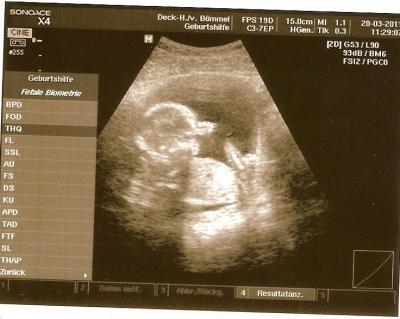

Hatte gestern und heute Blutungen und bin dann heute morgen dirket zum Fa gefahren, sie hatte mich dann gefragt obich starke blutungen hatte ich habe gesagt ja gestern und wieso ich dann nicht ins KH gefahren bin. Die ärztin fragte mich das auch habe gesagt nein bin ich nicht. Da sagte sie hätte auch nichts geändert. Sie hat dann noch mal ein Ultraschall gemacht und meiner Prinzessin geht es super habe halt nur 2 tage couch verordnet bekommen und magnesium soll ich nehmen lg jazz